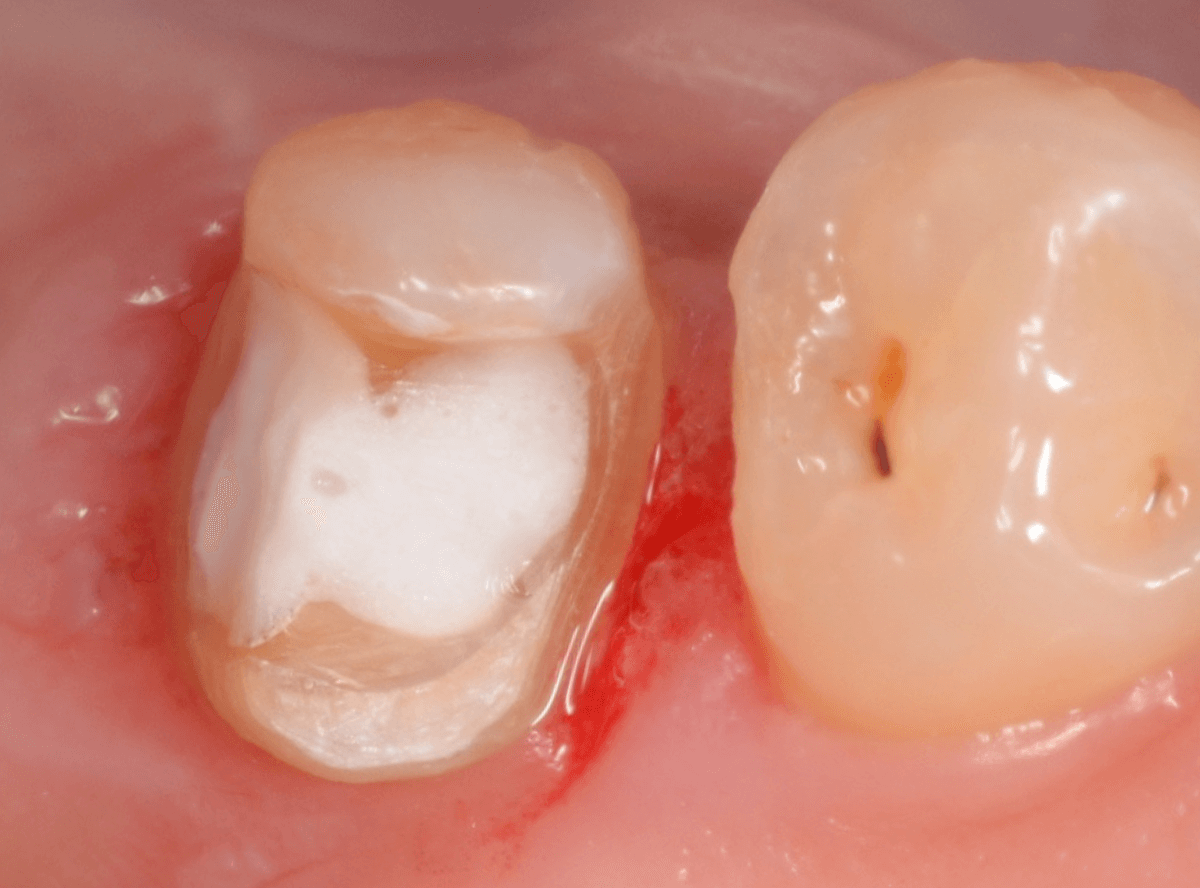

Case.29

舌のそばの虫歯とセラミック治療

下の奥歯が虫歯になった患者さんのケースです。

〇部が虫歯の部分です。

写真で見てわかるように、常に舌が歯に触っているような状況です。

このような場合、虫歯を見つけづらいですし、治療の難易度もあがります。

虫歯の治療を開始します。

隣の歯とのすき間を中心に広い虫歯になっていました。

虫歯治療後、特に症状もなく経過観察できましたので、つめものを作る治療に入ります。

セラミック治療をご希望されましたので、

小臼歯をE-MAX・インレー、

大臼歯をジルコニア・インレーで処置することになりました。